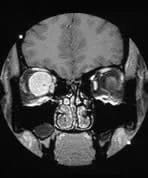

Right Orbital Mass

A patient presents with right-sided ocular pain and parietal headaches.

A large ovoid intraconal mass is shown in the right orbit. It does not extend intracranially or into the optic canal and it is transversed by the optic nerve. The appearances are most likely to be those of a glioma.